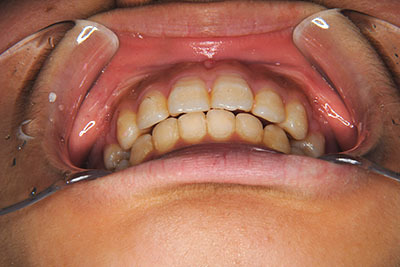

小学生高学年や中高生で矯正治療を考えている方へ

歯が乳歯から永久歯に生え変わった小学生高学年や、中高生でも矯正治療に手遅れということは全くありません。

成長中の顎の骨を矯正できたり、この時期の矯正はおとなになってから矯正治療を始めるよりも短期間で済むことがほとんどです。当院だとおおよそ1年で動的治療(マルチブラケット装置をつける期間)が終わることが多いです。